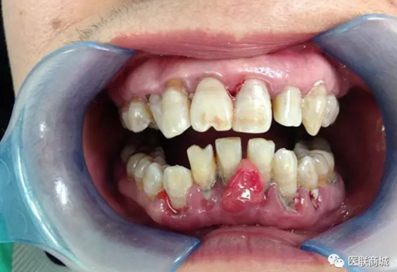

檢查:全口口腔衛(wèi)生差,牙齦紅腫,齦上牙石(+++),齦下牙石(+++),BOP(+),AL為3mm, BI=4,PD大于3mm,下中切牙間唇側(cè)可見如花生米樣大小腫物,碰觸出血,有蒂,基底寬,表面可見充血,下前牙松動(dòng)一度。上下牙列不齊,下前牙間可見間隙。深覆牙合3度。